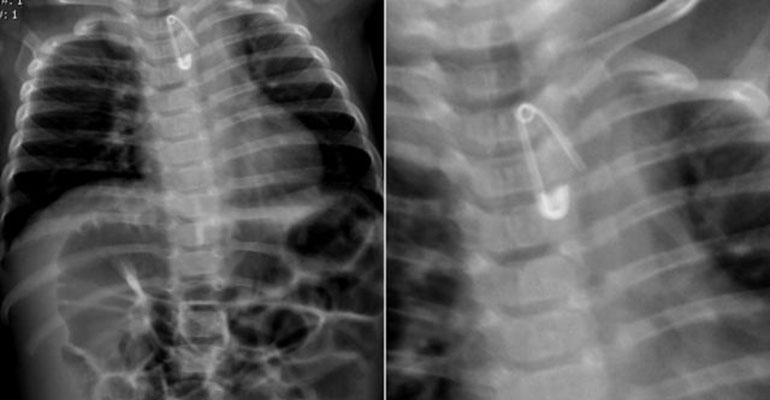

Pomocy w krotoszyńskim szpitalu szukali rodzice 6-miesięcznego dziecka. Malec połknął bowiem 2-centymetrową agrafkę. Rozwarta zapinka  ostrzem skierowanym ku dołowi – uwięzła w przełyku chłopczyka – co wskazywało zdjęcie rentgenowskie.